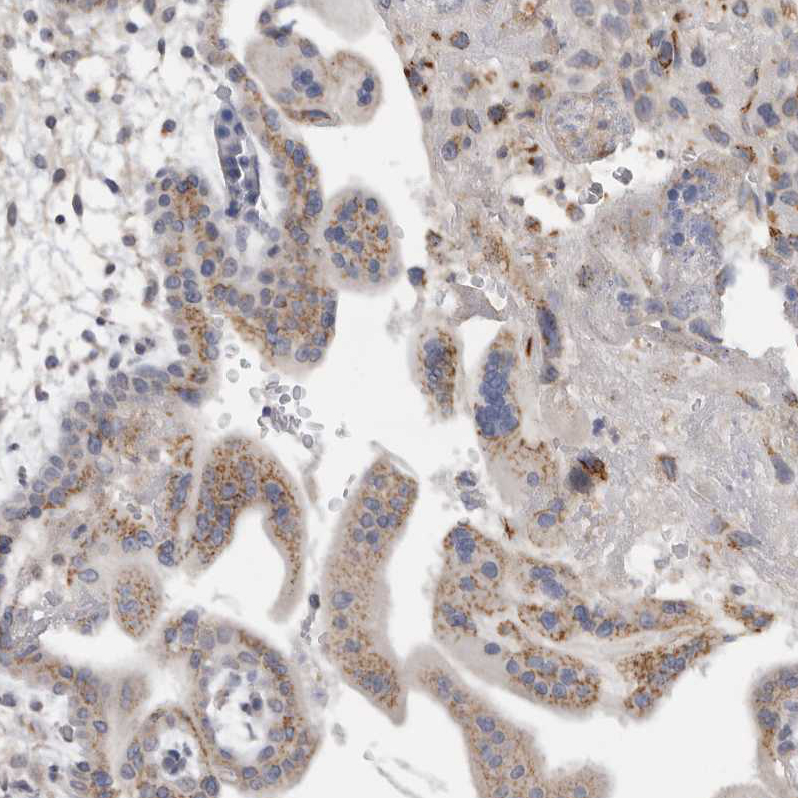

Immunohistochemical staining of human placenta shows moderate granular cytoplasmic positivity in trophoblastic cells.